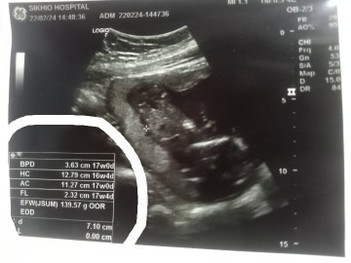

อันที่วงมันคืออะไรค่ะ ยังไม่ค่อยเข้าใจเลย มันคืออะไร ทำไมถึงมีสามอันค่ะ

ขนาดตามส่วนต่างๆที่เครื่องวัดคำนวนได้คะ